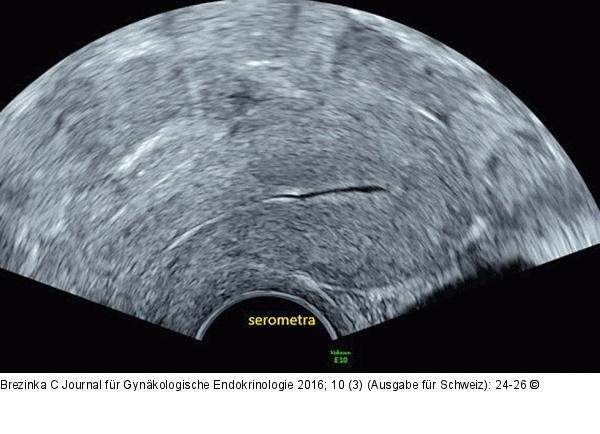

Abbildung 1: Ultraschall-Serometra Serometra bei Asherman-Syndrom nach manueller Plazentalösung und dreimaliger Abrasio nach der letzten Entbindung. Dank der Flüssigkeit kann man erkennen, dass praktisch keine Endometrium-Schleimhaut aufgebaut ist. |

Serometra bei Asherman-Syndrom nach manueller Plazentalösung und dreimaliger Abrasio nach der letzten Entbindung. Dank der Flüssigkeit kann man erkennen, dass praktisch keine Endometrium-Schleimhaut aufgebaut ist. |